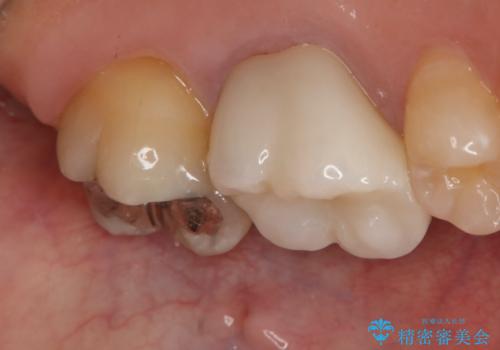

- 左上7番の銀歯をセラミックにやり変え希望の患者様です。

切削量・形態からセラミックインレーでの治療を計画しました。

銀歯とその直下のう蝕を除去した後、CRにて裏層しています。

インレー装着の際はラバーダムを使用しています。